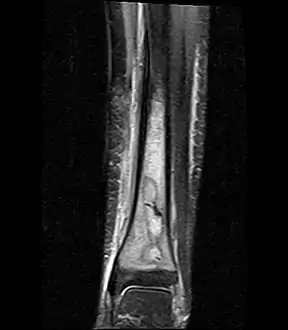

- Coronal fat suppressed STIR image showing, bone marrow and subcutaneous edema as well as subperiosteal edema. The thin hypointense rim surrounding the intramedullary collection represents the reactive interface between the abscess and the body's attempt to wall it off.